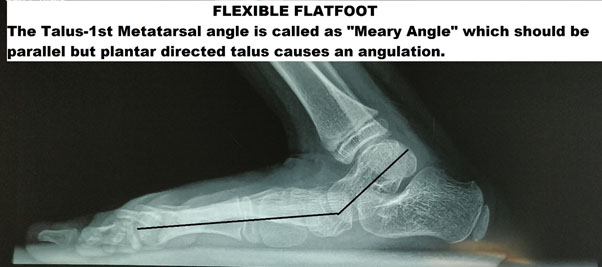

Investigations X-ray

Weight-bearing lateral/AP films will give as the idea of the relationship of the hindfoot to the forefoot. The talar axis should be parallel to the first metatarsal and is called the “Meary Angle.”